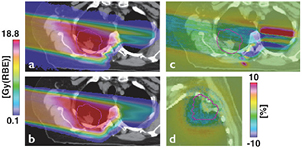

Because proton therapy plans are not optimized in RBE-weighted dose, expressed in Gy(RBE)7, biology is considered independently from the physics driven planning process using the RBE = 1.1 approximation and considering uncertainties. In C-ion therapy, instead, plans are optimized using the Gy(RBE). Essentially two different models are used for the calculation of the Gy(RBE): the Japanese centers use a model developed at NIRS, where the shape of the SOBP is based on in vitro cell killing experiments. The curve is then normalized using a region in the SOBP which is isoeffective to neutrons, whose clinical RBE was determined as 3 from previous clinical experience in Japan (Matsufuji et al 2007). On the other hand, the GSI Helmholtz Center in Darmstadt (Germany) developed a specific biophysical model (local effect model, or LEM), which predicts the RBE for different ions and tumor types starting from the corresponding clinical photon data and an amorphous track structure model (Krämer and Scholz 2000). Amorphous track structure models use average dose distributions along the track of the heavy ions, assuming that the dose decreases as r−2, where r is the track radius. Once the physical dose distribution is described, the biological response can be derived from x-ray survival curve, and the model can predict the effect of any ion. Already introduced by Bob Katz in the 60s (Butts and Katz 1967), these models are sometimes criticized by supporters of micro- or nano-dosimetry because they do not account for the high heterogeneity of the dose distribution at the nm level, already visible with x-rays (Beuve 2009). However, recent measurements of DNA damage distribution in vivo show that the predicted radial dose distribution corresponds to an observed biological damage distribution (Mirsch et al 2015). Amorphous track structure approximations remain therefore a simple and valid tool for prediction of charged particle effects starting from x-ray radiosensitivity. The LEM is able to reproduce the RBE of light and heavy ions for inactivation of cells with different intrinsic radiosensitivity, and has been improved many times in the past years (Grün et al 2012). It is currently being used in the C-ion therapy centers in Germany (Heidelberg and Marburg), Italy (Pavia), and China (Shanghai). An experimental intercomparison between NIRS and GSI using in vitro cells and mice provided comparable results, in agreement with the measured RBE (Uzawa et al 2009). However, the two models give different predictions of the Gy(RBE) when different fractionation schemes and tissue radiosensitivity are compared (Fossati et al 2012; Steinsträter et al 2012). In order to make use of the full potential of carbon beam scanning, NIRS has recently introduced a modified microdosimetric kinetic model (MKM) that can adapt optimization procedures to various biological parameters (Inaniwa et al 2015). This is particularly important for hypofractionation regimens, where the use of a dose-dependent RBE is necessary to take into account the reduced RBE at high dose/fraction (Friedrich et al 2014).

2.5.3. Treatment planning: physics and biology.

Treatment of a patient with pencil beam scanning is uniquely tailored for that patient and requires many different parameters. Each of these parameters has uncertainties. The error on the particle stopping power in a given tissue can shift 3–5% the prescribed range. Monte Carlo codes can be the ideal tools for precise plan calculations, but they must be faster to find daily clinical applications, and need accurate reaction cross-sections in useful target materials for the energy range of interest. Measurements of double-differential fragmentation cross sections are essential for heavy ion therapy, while target fragmentation is important also in protontherapy. These are 'classical' nuclear physics measurements, even if they are time-consuming and complex, and may represent a major contribution of 'old' nuclear physics to 'new' cancer therapy. In addition, new centers will try to exploit different ions beyond 1H and 12C, and treatment plans should add the ion atomic number Z to the optimization. However, the physical dose in Gy for charged particles does not reflect the biological effects in the tumor and the normal tissue. The plan optimization must also include the biological effectiveness of the beam, taking into account the intra-tumoral heterogeneity (hypoxia, cancer stem cell niches, etc). Development of robust radiobiological models is essential to exploit the full benefit of particle therapy, and require a careful physical characterization of the beam interaction down to the nm size. Beyond the RBE, major breakthrough can be expected by particle radiobiology, e.g. in the emerging field of radioimmunotherapy, and new biophysical models will be necessary to incorporate these new data.